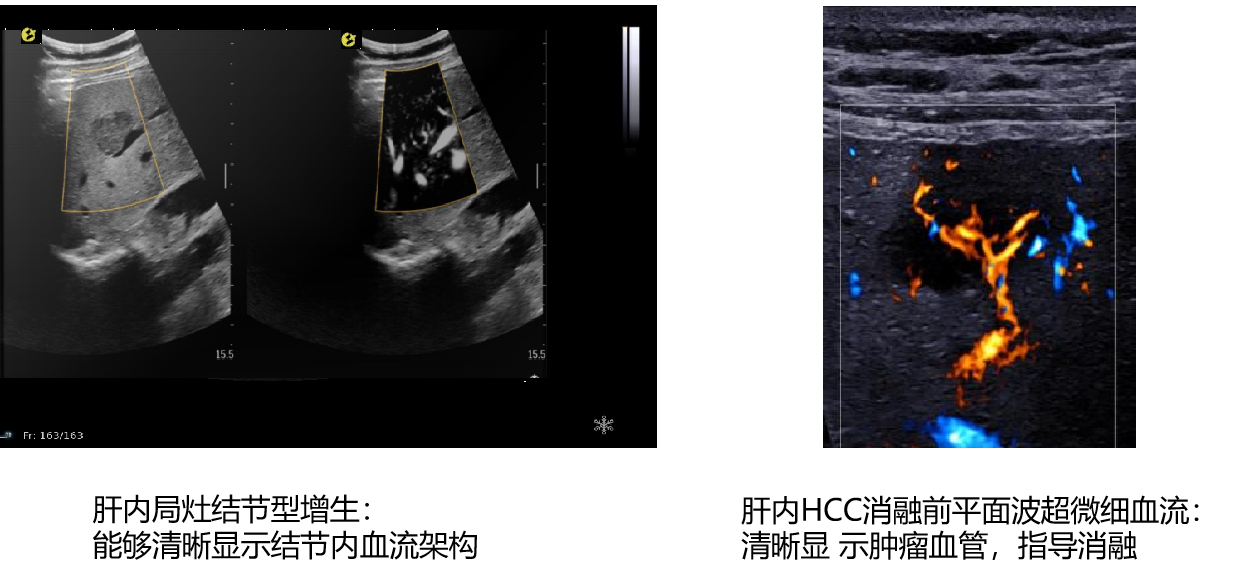

平面波超微细血流显像

能够提供更多真实的组织细小及末梢血管的血流信息,直观的观察组织内部的血管架构及血流形态的情况,提供临床更多有价值的诊断信息。

超声介入术前进针方案提供血流参考信息

超声介入术后疗效评估